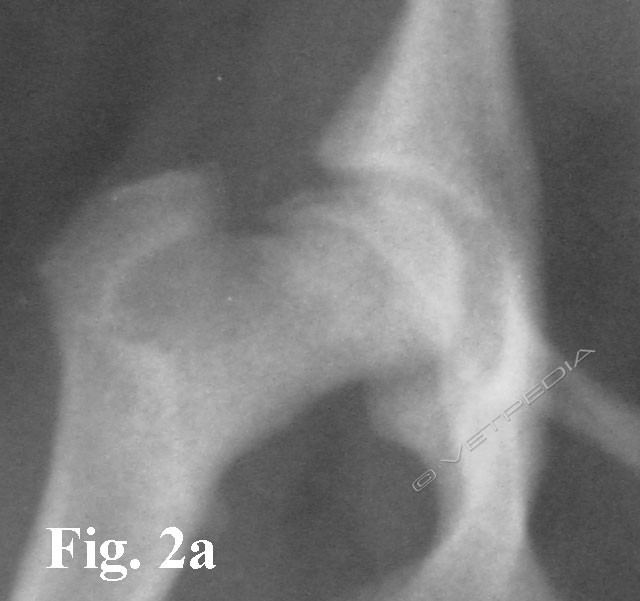

{{/_source.additionalInfo}}La necrosi asettica della testa del femore è anche denominata malattia di Legg Calvè Perthes e necrosi avascolare della testa del femore. Si tratta di un'affezione ortopedica coinvolgente l’articolazione coxofemorale di cani di razza toy o di piccola taglia durante il periodo dell’accrescimento, ad interessamento più frequentemente monola